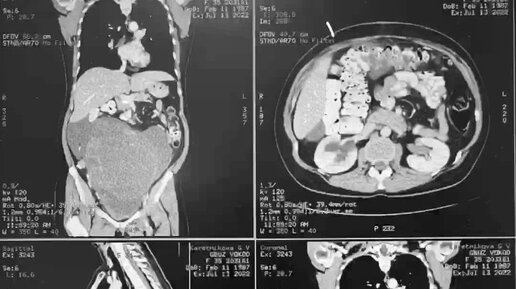

Метастаз колоректального рака